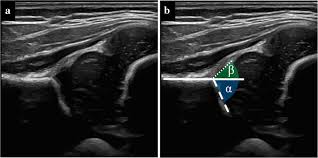

Ce reprezintă Unghiul Beta?

Dacă unghiul Alpha măsoară partea osoasă a șoldului, unghiul Beta oferă informații despre partea cartilaginoasă (sprânceana acetabulară). O valoare normală pentru unghiul Beta este, de obicei, sub 55 de grade.